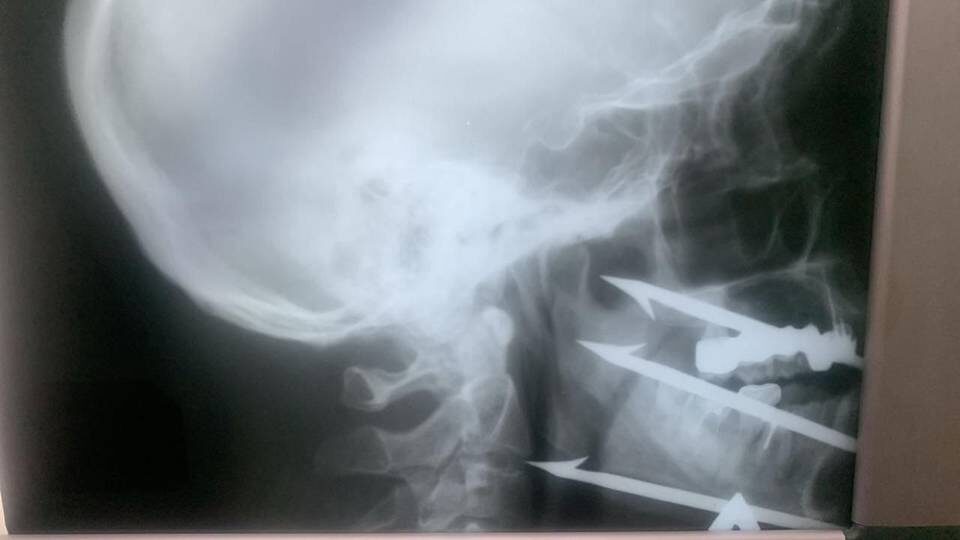

Волгоградские хирурги спасли рыбака с гарпуном в лице

Как сообщает МТВ.ОНЛАЙН со ссылкой на пресс-службу медучреждения, 52-летний мужчина случайно выстрелил себе в лицо из подводного ружья, и трёхзубый гарпун, пронзив мягкие ткани, остановился буквально в миллиметре от сонной артерии. Угроза жизни была крайне высока — малейшее смещение снаряда могло привести к фатальному исходу.

В экстренном порядке была собрана объединённая бригада специалистов: операцию выполнили челюстно-лицевой хирург Волгоградской городской клинической больницы № 1 Роман Стасюк, признанный лучшим хирургом региона в 2025 году, и сосудистый хирург больницы № 25 Олег Виноградов. Врачам удалось аккуратно извлечь инородное тело, сохранив жизненно важные сосуды и нервы. Сейчас пациент находится в стабильном состоянии и проходит восстановление.

Фото: пресс-служба Волгоградской городской клинической больницы № 1